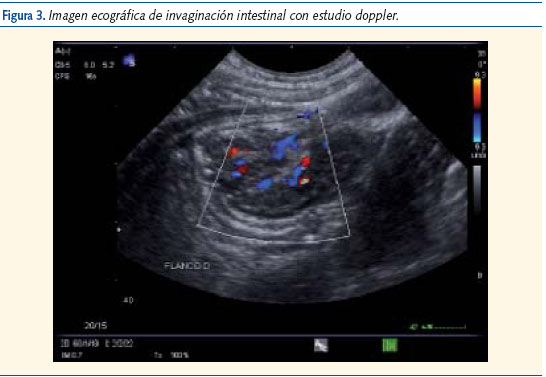

Evolución: durante su observación en urgencias presenta 4 vómitos y tendencia al sueño; se mantiene afebril en todo momento. Se le realiza una ecografía abdominal (figuras 1, 2 y 3) en la que se observa una invaginación ileo-ileal y es remitido al servicio de cirugía pediátrica del hospital de referencia, donde se repite la ecografía. No se encuentran entonces signos de dicha invaginación pero sí varias adenopatías mesentéricas. El paciente permaneció en observación 24 horas y fue dado de alta sin complicaciones.

De forma clásica, se considera que el gold standard para el diagnóstico es el enema opaco, si bien la ecografía abdominal ha desplazado a éste por ser menos invasiva2.

Podemos concluir que la invaginación intestinal puede cursar con sintomatología neurológica en la población pediátrica, por lo que ante inexplicables alteraciones del nivel de conciencia sin signos de focalidad neurológica, debemos considerar los cuadros abdominales dentro de nuestro diagnóstico diferencial. La ecografía es una técnica diagnóstica poco invasiva que puede ayudar en el diagnóstico diferencial de cuadros de abdomen agudo con sintomatología neurológica inexplicada en niños pequeños.